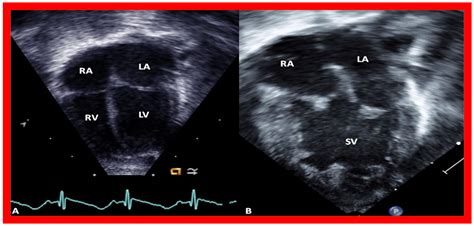

To grasp the implications of Double Inlet Left Ventricle, it is helpful to visualize the normal circulatory system. In a typical heart, the right side pumps oxygen-poor blood to the lungs, while the left side pumps oxygen-rich blood to the rest of the body. In a patient with DILV, the blood from both the right and left atria flows into the same large ventricular chamber. Because this single chamber is responsible for pumping blood to both the lungs and the entire body, the heart faces a unique challenge in maintaining systemic pressure and lung circulation.

Modern advancements in pediatric cardiology have made early detection of Double Inlet Left Ventricle much more accurate. In many cases, the condition is identified during a prenatal fetal echocardiogram, allowing for a planned delivery at a specialized cardiac center. After birth, infants are monitored closely through a variety of diagnostic tools.

• double inlet lv echo